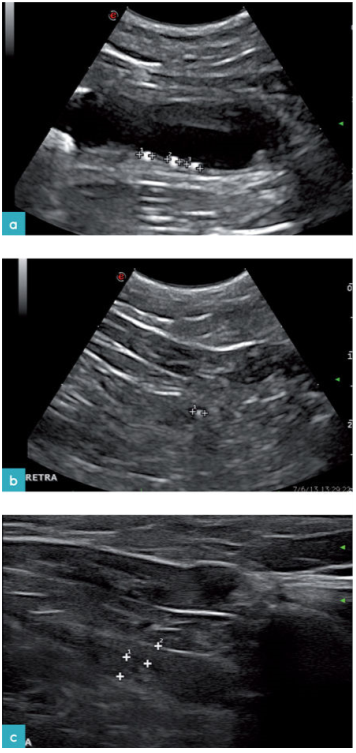

膀胱颈向后延伸成为尿道。与犬相比,猫的腹腔内尿道段更长(图3)。超声无法分辨出尿道的组织学分层。尿道是一个从膀胱颈延伸到骨盆腔的管状结构(图4)。